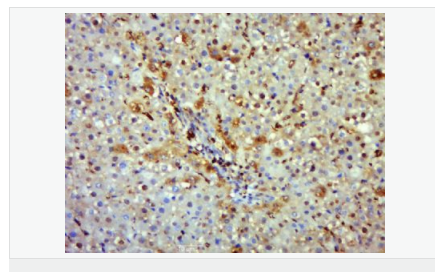

交叉反應(yīng):Human,Mouse,Rat(predicted:Dog,Pig,Horse,Sheep) 推薦應(yīng)用:WB,IHC-P,IHC-F,ICC,IF,Flow-Cyt

| 產(chǎn)品應(yīng)用 | WB=1:500-2000 IHC-P=1:100-500 IHC-F=1:100-500 Flow-Cyt=1μg/Test ICC=1:100-500 IF=1:100-500 (石蠟切片需做抗原修復(fù)) not yet tested in other applications. optimal dilutions/concentrations should be determined by the end user.  |

| 產(chǎn)品介紹 | Nitric oxide (NO) is an inorganic, gaseous free radical that carries a variety of messages between cells. Vasorelaxation, neurotransmission and cytotoxicity can all be potentiated through cellular response to NO. NO production is mediated by members of the nitric oxide synthase (NOS) family. NOS catalyzes the oxidization of L-arginine to produce L-citrulline and NO. Two constitutive isoforms, brain or neuronal NOS (b or nNOS, type I) & endothelial cell NOS (eNOS, type III), and one inducible isoform (iNOS, type II), have been cloned. All NOS isoforms contain calmodulin, nicotinamide adenine dinucleotide phosphate (NADPH), flavin adenine dinucleotide (FAD), and flavin mononucleotide (FMN) binding domains. Nitric oxide synthase is expressed in liver, macrophages, hepatocytes, synoviocytes, stimulated glial cells and smooth muscle cells. Cytokines such as interferon-gamma (IFN), tumor necrosis factor (TNF), interleukin-1 and -2, and lipopolysaccarides (LPS) cause an increase in iNOS mRNA, protein, and activity levels. Protein kinase C-stimulating agents exhibit the same effect on iNOS activity. After cytokine induction, iNOS exhibits a delayed activity response which is then followed by a significant increase in NO production over a long period of time. Human iNOS is regulated by calcium/calmodulin (in contrast with mouse NOS2). Function: Produces nitric oxide (NO) which is a messenger molecule with diverse functions throughout the body. In macrophages, NO mediates tumoricidal and bactericidal actions. Also has nitrosylase activity and mediates cysteine S-nitrosylation of cytoplasmic target proteins such COX2. Subunit: Homodimer. Binds SLC9A3R1. Tissue Specificity: Expressed in the liver, retina, bone cells and airway epithelial cells of the lung. Not expressed in the platelets. Similarity: Belongs to the NOS family. Contains 1 FAD-binding FR-type domain. Contains 1 flavodoxin-like domain. SWISS: P35228 Gene ID: 4843 Database links: Entrez Gene: 4843 Human Entrez Gene: 18126 Mouse Omim: 163730 Human SwissProt: P35228 Human SwissProt: P29477 Mouse Unigene: 709191 Human Unigene: 2893 Mouse Unigene: 10400 Rat Important Note: This product as supplied is intended for research use only, not for use in human, therapeutic or diagnostic applications. 合成與降解(Synthesis and Degradation) 催化生物體內(nèi)一氧化氮(NO)生成的酶。分神經(jīng)型一氧化氮合成的酶(nNOS or NOS-1)、誘導(dǎo)型一氧化氮合成的酶(iNOS or NOS-2)、內(nèi)皮型一氧化氮合成的酶(eNOS or NOS-3)。  |